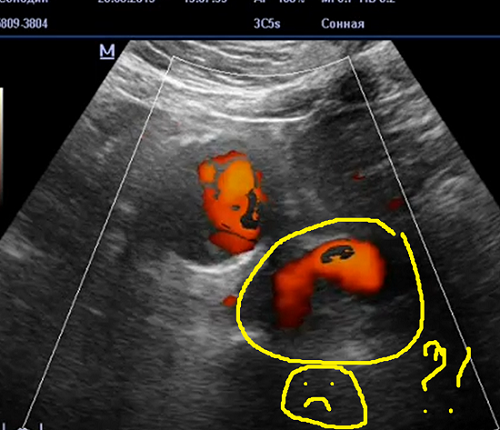

Аааа пачему вы живот смотрите на пресете каротид?

Вы можете объяснить последнюю сонограмму по другому?

Я вас внимательно слушаю!

то что вы тут усиленно рисуете - ложный канал в тромбе

Давайте я еще подкину идею.

А может это еще и ложная аневризма образовалась в добавок к простой аневризме?